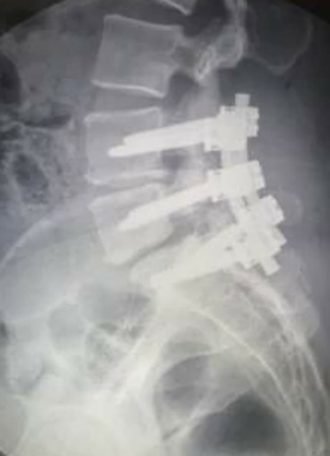

I urgently needed spine fusion of L4/5/S1, and now have 2 rods and 6 titanium screws that hold my lower back in place. There are no words to describe this surgery and very long recovery, but I will not let it define me.